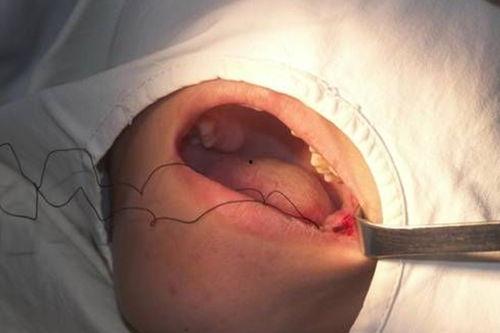

首先,医生会给你进行局部麻醉,让你在拔牙过程中不会感到疼痛。麻醉过后,医生会使用特殊的工具,将智齿从牙槽骨中取出。

这个过程可能会持续几分钟到十几分钟不等,具体时间取决于智齿的生长情况和拔牙难度。在这个过程中,你可能会听到一些声音,比如拔牙工具与牙齿摩擦的声音,但不用担心,这些都是正常的。